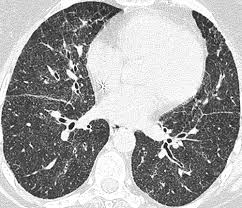

Frontiers Sarcoidosis As An Autoimmune Disease Immunology from www.frontiersin.org It typically affects young adults and initially presents with one or more of the following. Helen has now had treatment for her lung cancer and is recovering well. A case of primary lung cancer associated with sarcoidosis. We report a patient with concomit. Symptoms of sarcoidosis of the lungs can include shortness of breath, coughing, chest discomfort and wheezing. The decrease in other more severe symptoms is wheezing which if. For these people, the symptoms are not usually severe. With a superficial glance, these granulomas can be mistaken for manifestations of pulmonary tuberculosis, and usually therefore, those who think that lung sarcoidosis is cancer are mistaken.

View Of Coal Worker S Pneumoconiosis And Sarcoid Like Reaction Mimicking Lymph Node Metastases In A Patient With Lung Cancer A Case Report The Southwest Respiratory And Critical Care Chronicles from pulmonarychronicles.com Or small cell cancer metastasis or a sarcoid like reaction in our patient. The cause of sarcoidosis is unknown. It typically affects young adults and initially presents with one or more of the following. If your sarcoidosis goes into remission, meaning you no longer have any symptoms, your doctor may choose to slowly stop your medications. Because sarcoidosis can escape diagnosis or be mistaken for several other diseases, we can only guess at how many people are affected. Sarcoidosis is an inflammatory disease that affects one or more organs but most commonly affects the lungs and lymph glands. Secondhand smoke causes lung cancer in adults who have never smoked. Sarcoidosis is a disease involving abnormal collections of inflammatory cells that form lumps known as granulomata.

Sarcoidosis is a chronic inflammatory condition that may increase the risk of cancer, but limited information is available on occurrence of cancer in results were generally consistent among ethnic groups, although the increased risk of colon and kidney cancer was observed only in white patients. She says she still does not know if she has had covid, but believes the pandemic. Managing sarcoidosis involves monitoring your symptoms closely to track the effectiveness of treatments. Board certification in internal medicine. The disease is referred to as systemic lesions. Read about sarcoidosis, a chronic lung disease. Sarcoidosis is a multisystem granulomatous disorder of unknown etiology that affects individuals worldwide and is characterized pathologically by the presence of noncaseating granulomas in involved organs. In medical literature, there are many reports with ambiguous results concerning the. Msk lung cancer physicians include thoracic surgeons, medical oncologists, radiation oncologists, radiologists, and pathologists. Because sarcoidosis can escape diagnosis or be mistaken for several other diseases, we can only guess at how many people are affected. Sarcoidosis is often identified as swollen hilar lymph nodes found in chest radiography during routine physical checkups. Sarcoidosis most often affects the lungs and may cause lung problems, such as: Sarcoidosis is currently thought to be associated with an abnormal immune response.